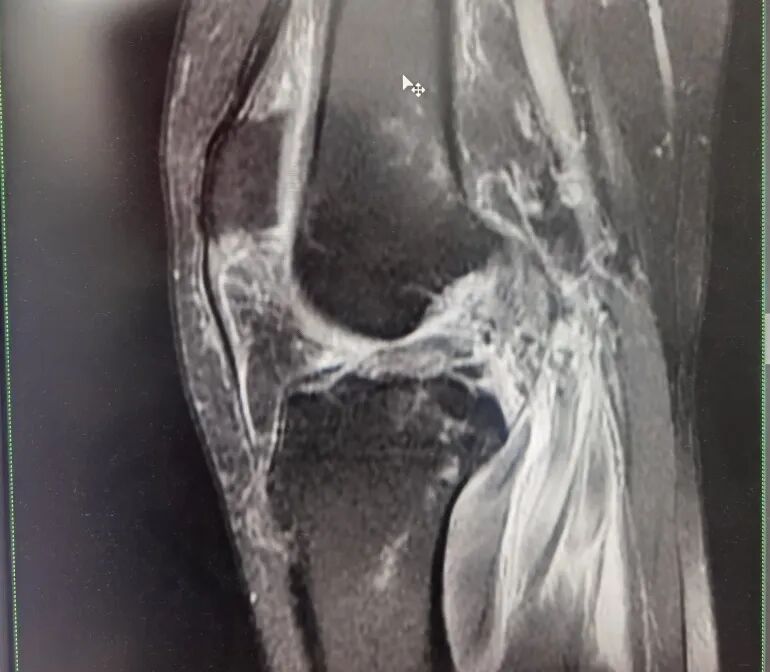

進一步完善檢查,發(fā)現(xiàn)患者除頭部損傷外,左膝嚴重損傷,其左膝“內(nèi)側(cè)半月板撕裂,外側(cè)半月板撕裂”,左膝關(guān)節(jié)“內(nèi)側(cè)副韌帶完全斷裂,前十字韌帶斷裂,外側(cè)副韌帶損傷”伴“左側(cè)髕韌帶損傷”。

骨科王懷波主任解釋,患者受傷后疼痛難忍,因外傷導(dǎo)致膝關(guān)節(jié)功能嚴重受限,關(guān)節(jié)穩(wěn)定性嚴重喪失,活動時伴有恐懼感。經(jīng)運動醫(yī)學詳細查體,結(jié)合膝關(guān)節(jié)MRI提示,患者遭遇了前交叉韌帶,內(nèi)側(cè)副韌帶,內(nèi)外側(cè)半月板聯(lián)合損傷,屬于膝關(guān)節(jié)嚴重復(fù)合傷。“前交叉韌帶又稱前十字韌帶,作為膝關(guān)節(jié)里面重要的韌帶之一,是膝關(guān)節(jié)從脛骨前方到股骨的后方的一根斜韌帶,可以控制膝關(guān)節(jié)旋轉(zhuǎn)。損傷的原因主要包括運動損傷和車禍損傷,最常見的損傷是股骨止點的撕裂。當前交叉損傷以后,病人對于加速跑、旋轉(zhuǎn)都會喪失功能?!?/p>